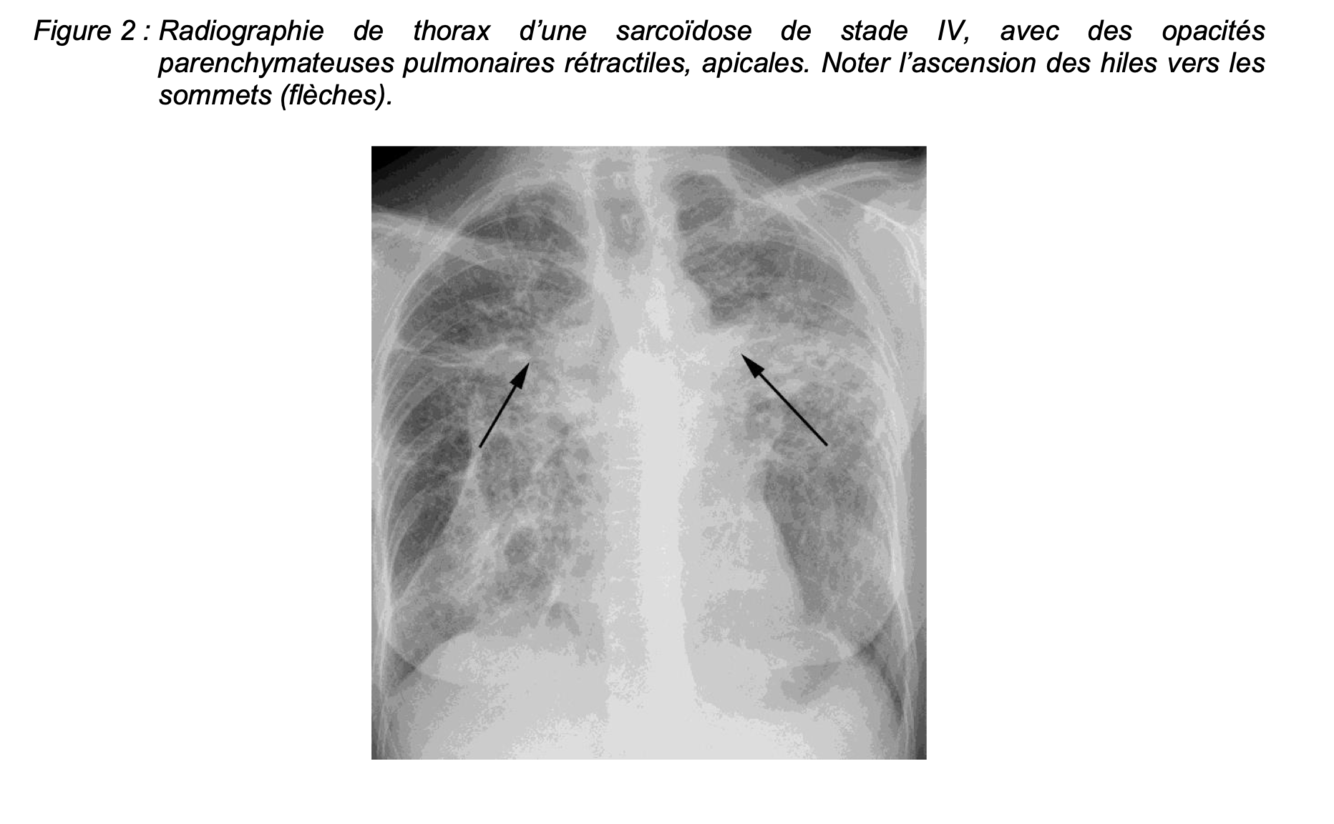

+ La fibrose, quand elle est présente :

▪ prédomine dans les parties supérieures et postérieures des poumons

▪ réalise des opacités parenchymateuses rétractiles avec ascension des hiles pulmonaires, une distorsion broncho-vasculaire, parfois des masses pseudo-tumorales péri hilaires ou un aspect en rayon de miel apical (Figure 2)

=> Figure 2